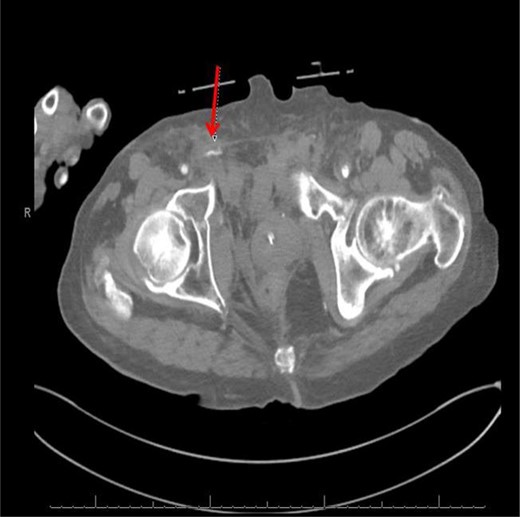

CT abdomen/pelvis with contrast was performed and a blush of contrast was noted posterior to the right pubic bone. Prior to taking patient for exploratory surgery, he was transferred to the interventional radiology suite where a pelvic angiogram was performed revealing an abnormal blush localized to the distal branches of the right iliolumbar artery (Fig. 2). Delayed phase of the angiogram demonstrated early venous filling consistent with a traumatic arteriovenous fistula which was embolized with 300–500 µ of embospheres and three 3 × 2 microcoils (Figs 3 and 4).

CT angiogram delayed phase of angiogram shows early venous filling consistent with AV fistula.